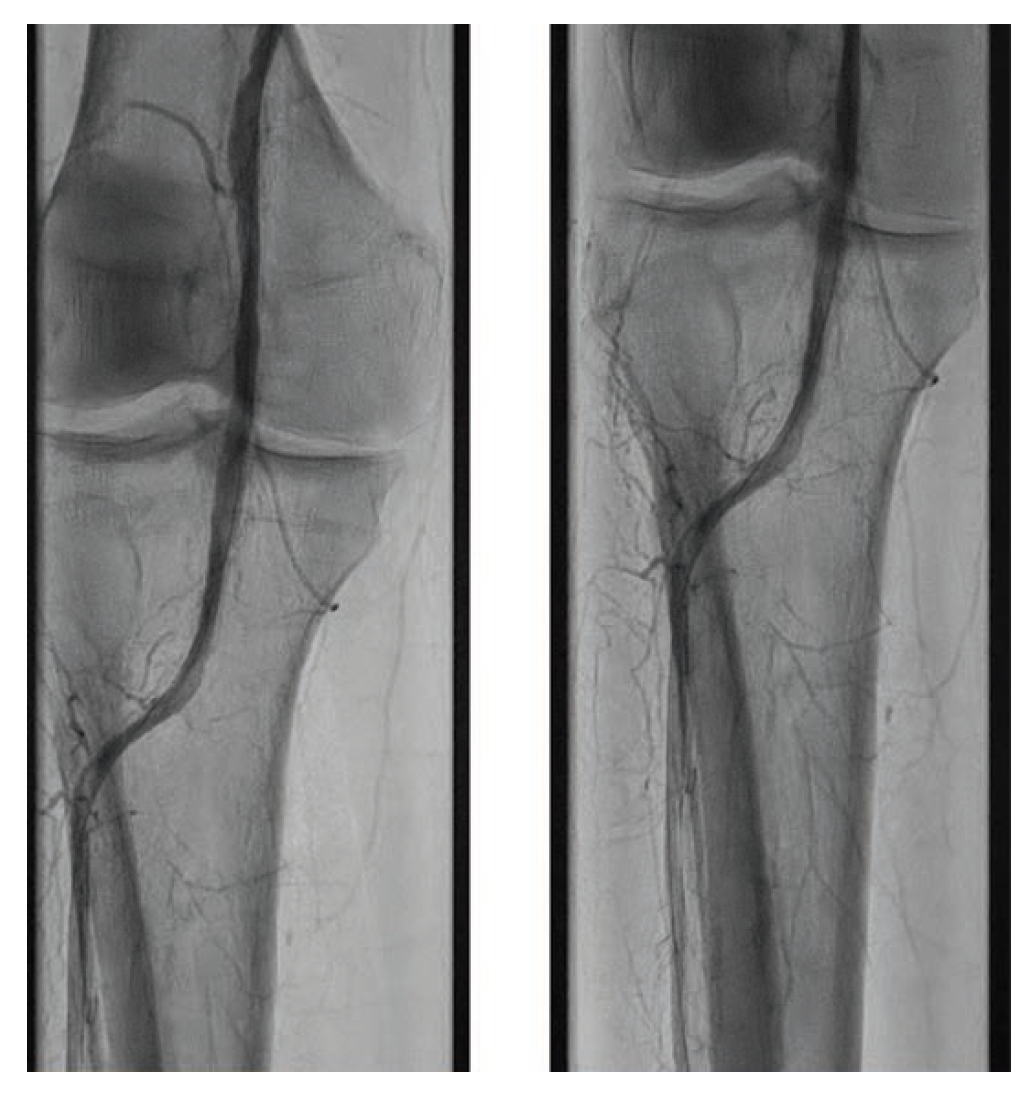

After the wire exchange, we attempted to aspirate, then flush, the 6F sheath with heparinized saline. After multiple failed attempts at sheath aspiration, we suspected a clotted arterial sheath and immediately proceeded to sheath exchange with a new 6F 45 cm sheath. Cautious to maintain wire position, the sheath was successfully exchanged. Saline flushing of the removed sheath resulted in expulsion of extensive clot burden (Figure 5). Repeat ACT confirmed therapeutic anticoagulation. The procedure concluded with percutaneous transluminal angioplasty followed by stenting of the SFA with BioMimics 6 x 150 mm stents (Figure 6). Final angiography demonstrated brisk flow through the SFA, popliteal, and anterior tibial arteries with no evidence of distal embolization (Figure 7 and Figure 8).